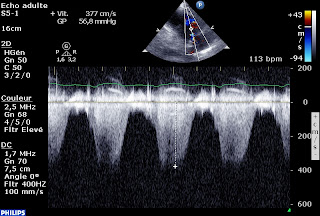

Une Vmax de le CIV à 3,6 m/sec, soit un gradient VG-VD à 55mmHg, donc une PAPs à 75 mmHg, si la pression artérielle systolique (qui est égale à la PVGs en l’absence de RAC) est à 130 mmHg.

Sur l’IT, la PAPs est calculée à 70 mmHg